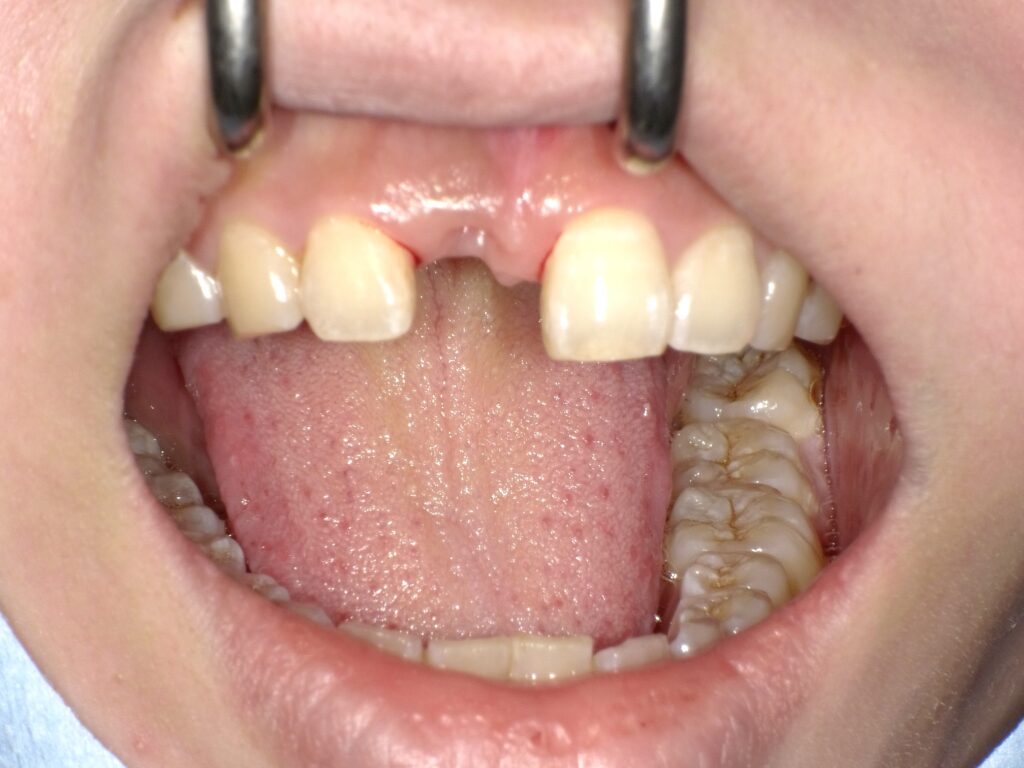

症例一覧 インプラント症例2 2024.11.25 治療内容インプラント主訴前歯事故で折れたのでインプラント治療を行いたい費用¥946,000(1本)治療期間7ヶ月 インプラント症例3 前の記事 インプラント症例1 次の記事